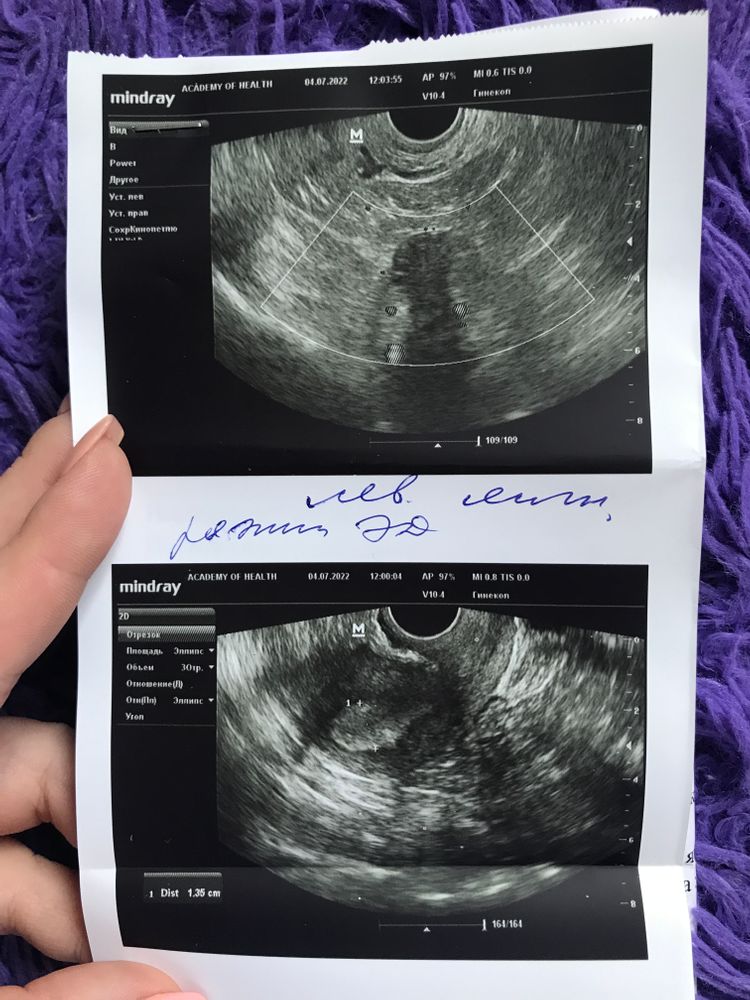

Всем привет. Была стимуляция овуляции с 5 по 9 дц клостилбегитом, на 16 ДЦ ДФ 19,5 мм сделали укол хгч 10000 ЕД, с этого же дня назначили пить Дюфастон до 28 ДЦ (по 2 т в день). Сходила сегодня на узи 20ДЦ фоликулы сдулись, кист нет, как и желтого тела (сказали все хорошо для данного дня цикла). Так же назначили прийти на узи через 4 дня, проверить ЖТ. У кого так было и получилось ли забеременеть? После укола ХГЧ все признаки овуляции были спустя 24-30 часов. Диагноз СПКЯ, первая стимуляция

Как нет жт, если у вас в ля написано, что есть) возможно, что о была незадолго до узи и оно формируется.

Ирис_Ка, согласна, что написали так, но почему то узистка сказала, что жт не сформировано (назвала это рассветом жт) и что нет кист. В общем не понятно все. Буду выжидать время и поход к своему врачу. А овуляция по ощущениям была в сб, возможно ещё рано и действительно у меня там все формируется ещё. Буду по крайне мере надеяться на это 😁🤞🏼